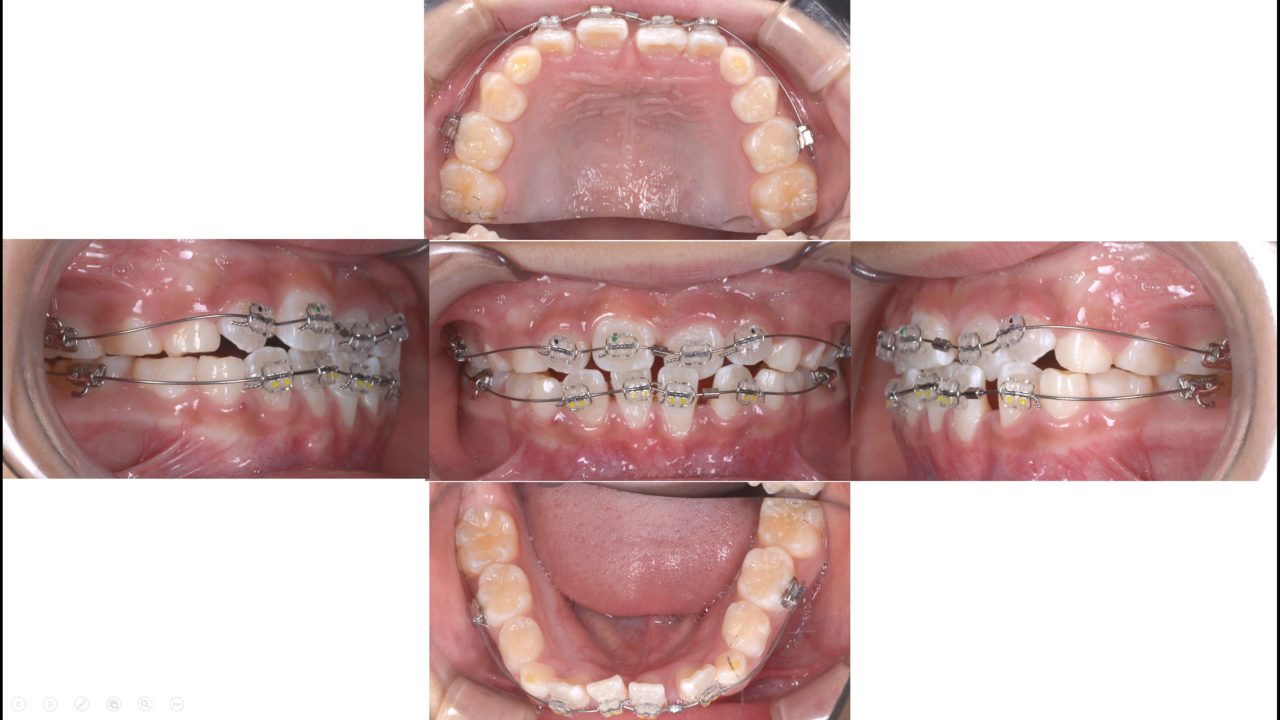

マルチブラケット 2020.6.3

スペースはできたので、マルチブラケットによる歯列改善を行った。

第1期治療終了 2020.8.14

前歯が正常咬合であり、叢生がない状態を確立した。今後はメインテナンスで側方歯永久歯の萌出を管理する